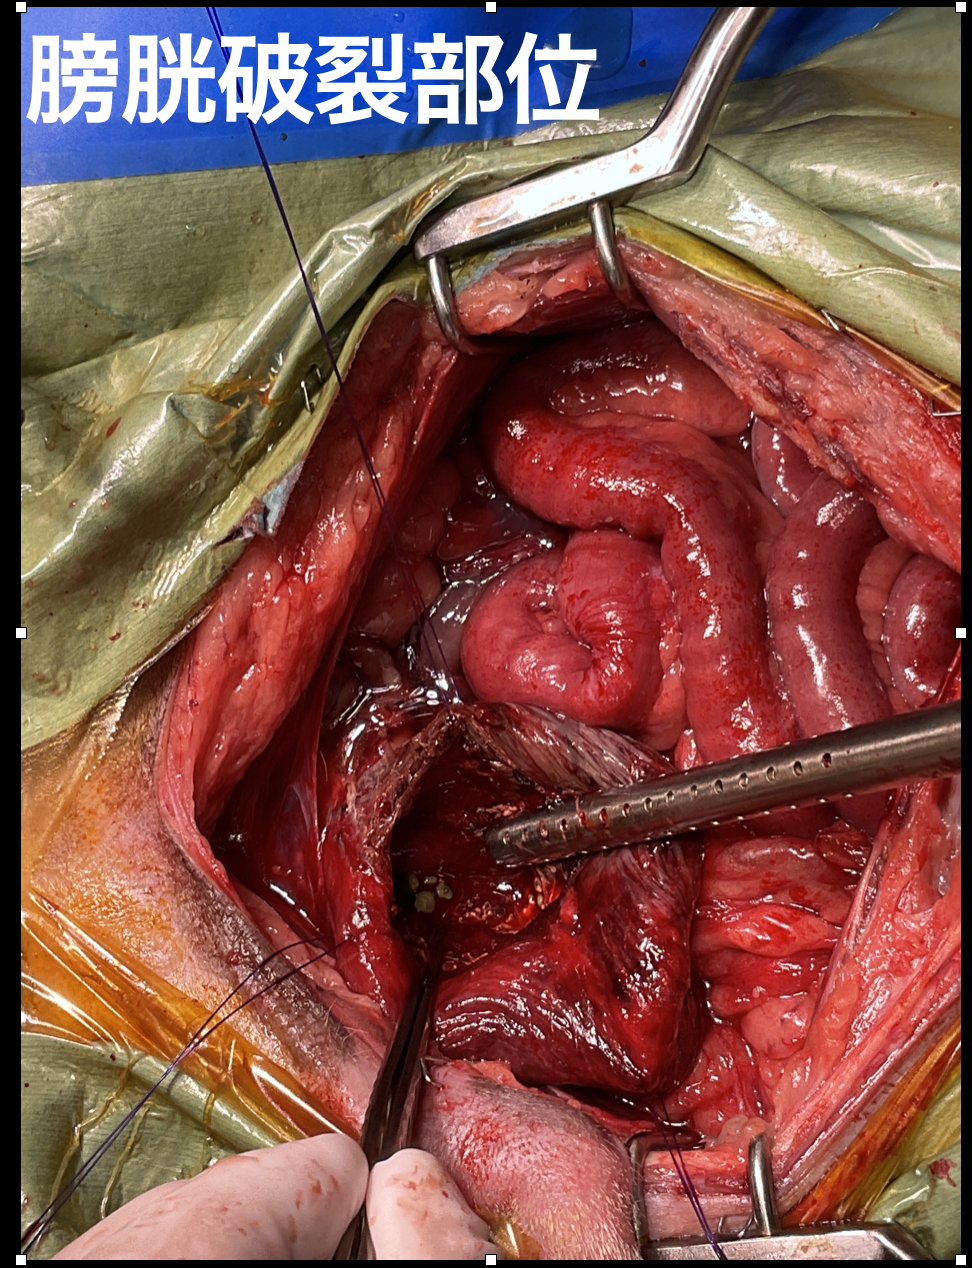

尿道結石による膀胱破裂

2歳、ダルメシアン、去勢雄のワンちゃんが、膀胱破裂の治療のため来院。

食欲不振、元気消失、嘔吐を主訴に動物病院を受診し、腹水貯留の精査のためCT撮影、導尿処置によって尿道閉塞による膀胱破裂と診断されました。

膀胱は顕著に暗赤色~赤色に変色しており、周囲組織との癒着を認めました。膀胱腹側に破裂部位を認め、 膀胱内の結石を摘出、膀胱は血流が確認される部位まで切除し縫合しました。